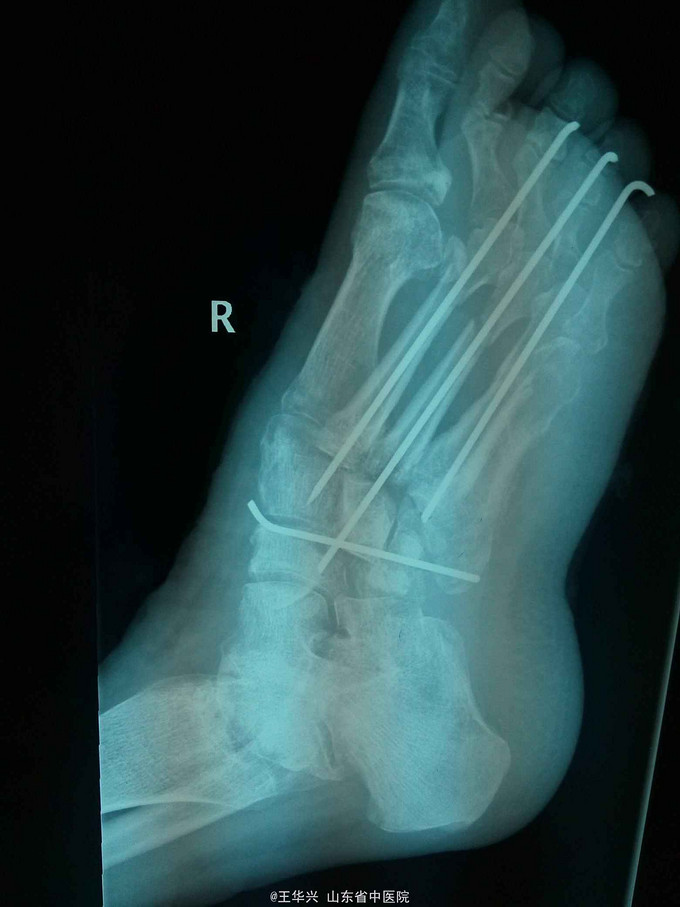

查体:左足疼痛,功能活动受限,伴有大面积软组织损伤,软组织向外侧翻转,足部前侧可见5*3cm软组织缺损,患处麻木感,足背动脉不可及。 辅助检查:x线 左足第2,3,4跖骨骨折

诊断:左足毁损伤 治疗:入院时已达到截肢标准,但患者家属不能接受,遂行常规手术。多次清创,行急症手术,给予简单钛针固定,软组织损伤给予原位缝合。细菌培养结果,万古霉素敏感,万古霉素局部填塞创口换药,术后给予多次清创,清除坏死组织及vsd负压吸引。待左足缺损区软组织条件可,行交腿皮瓣。